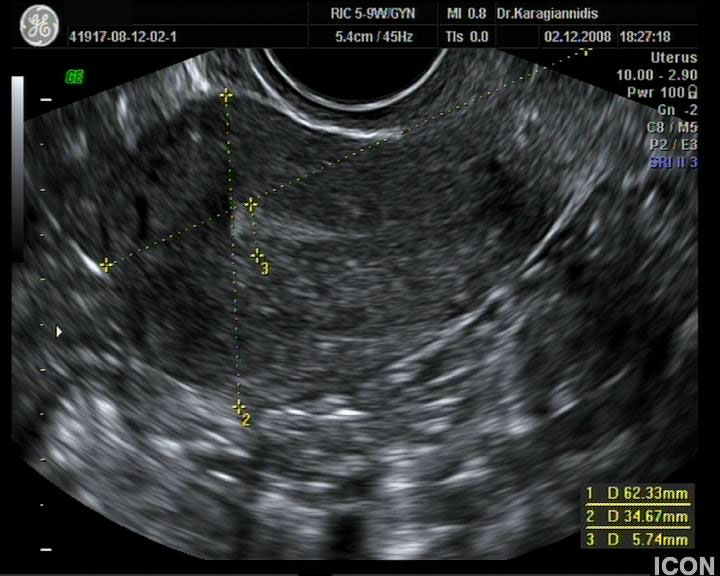

Αυχενική διαφάνεια

Η αυχενική διαφάνεια (ΑΔ) είναι η συλλογή υγρού στον τράχηλο του εμβρύου και συγκεκριμένα ανάμεσα στο δέρμα και στους ιστούς που καλύπτουν τη σπονδυλική στήλη.